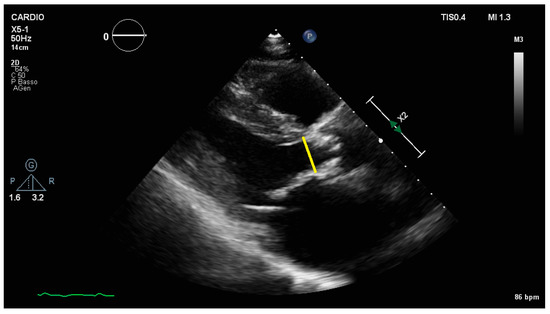

2.1. Transvalvular Pressure Gradients

2.2. Aortic Valve Area